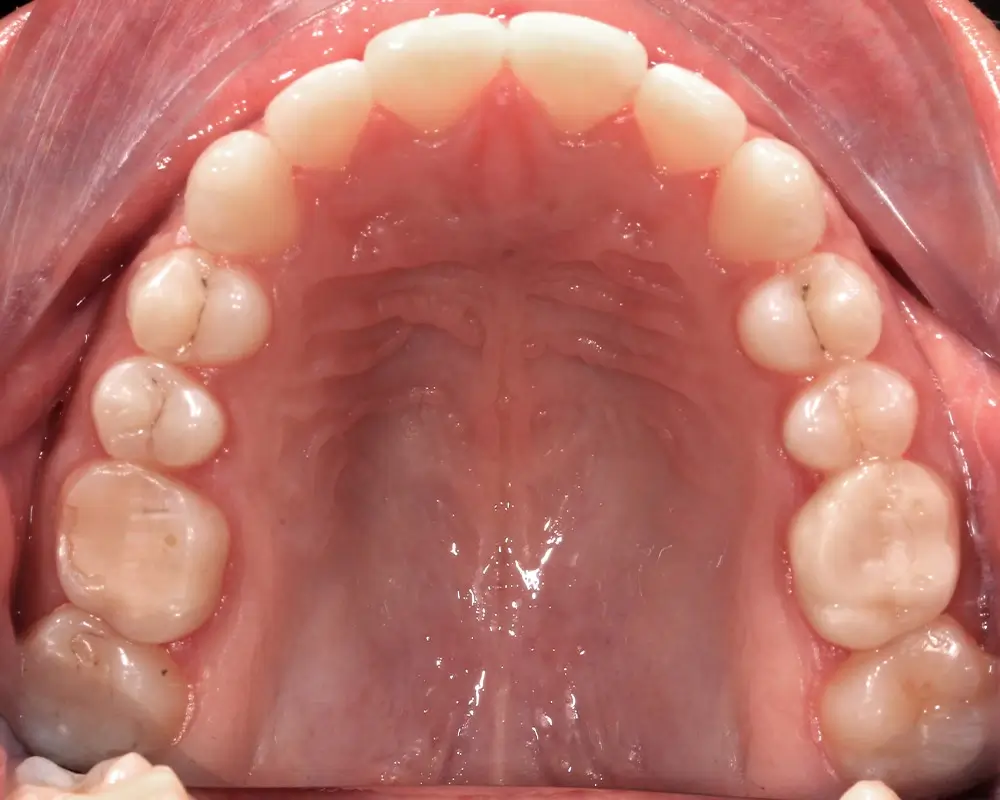

Открытый прикус - Кейс 5

Эффективность устранения дефекта прикуса посредством элайнеров FlexiLigner.

Результаты лечения